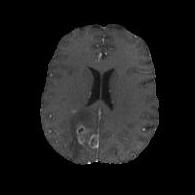

(a) (b) (c) (d)

Boundary Stream:

Fig. 2 demonstrates the output of each of the attention layers in our dedicated boundary stream. In essence, each attention layer progressively localizes the tumor and refines the boundaries. The first attention layer has learned rough estimate of the boundaries around the tumor and localized it, whereas the second and third layers have learned more fine-grained details of the edges and boundaries, refining the localization. Moreover, since our architecture leverages a dilated spatial pyramid pooling to merge the learned feature maps of the regular segmentation stream and the boundary stream, multiscale regional and boundary information have been preserved and fused properly, which has enabled our network to capture the small structural details of the tumor.

(a) (b) (c) (d) (e)

Comparison to Competing Methods:

We have compared the performance of our model against the most popular deep learning-based semantic segmentation networks, U-Net [9] and V-Net [7] (Fig. 3). Our model outperforms both by a considerable margin in all evaluation metrics. In particular, U-Net performs poorly in most cases due to the high false positive of its segmentation predictions, as well as the imprecision of its boundaries. The powerful residual block in the V-Net architecture seems to alleviate these issues to some extent, but V-Net also fails to produce high-quality boundary predictions. The emphasis of learning useful edge-related information during the training of our network appears to effectively regularize the network such that boundary accuracy is improved.